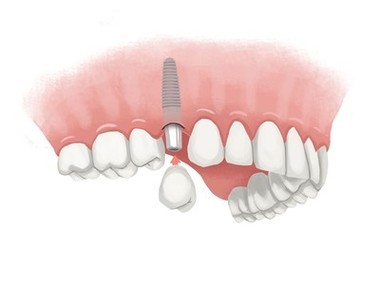

Can a failed dental implant be replaced?

How do you fix a failed dental implant?

For severe cases, your dentist will usually need to perform a bone grafting procedure before replacing the failed implant. Bone grafting is a process in which a new bone is grown.